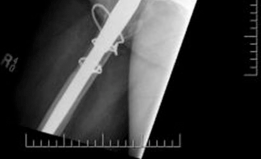

A highly porous metal cup is then impacted into the defect. The cup is often placed in an off-axis orientation, prioritizing host bone contact and initial stability over anatomic version and inclination. The subsequent cementation of the liner into the cage will correct the final articular geometry. If large cavitary defects remain behind the cup, highly porous metal augments or impacted cancellous allograft are utilized to fill the voids and support the primary shell. Multiple multi-hole screws are placed through the cup into the superior dome and posterior column to maximize initial fixation.

Cage Contouring and Fixation

The appropriate cage is selected based on preoperative templating and intraoperative trialing. The inferior flange is contoured to fit into the prepared ischial slot. The superior flange is contoured to lie flush against the lateral aspect of the ilium. Proper contouring is critical; a poorly contoured cage will experience high bending moments and subsequent fatigue failure.

The cage is inserted by first seating the inferior flange into the ischium. The superior flange is then impacted against the ilium. The cage should sit intimately against the previously placed highly porous cup. Fixation begins with the placement of cortical or cancellous screws through the superior flange into the dense bone of the ilium, aiming toward the sacroiliac joint. Screws are also placed through the central dome of the cage, passing through the cage, the underlying porous cup, and into the host bone, effectively locking the two components together. Care must be taken to avoid the superior gluteal neurovascular bundle during superior flange screw placement and the external iliac vessels during anterior screw placement.